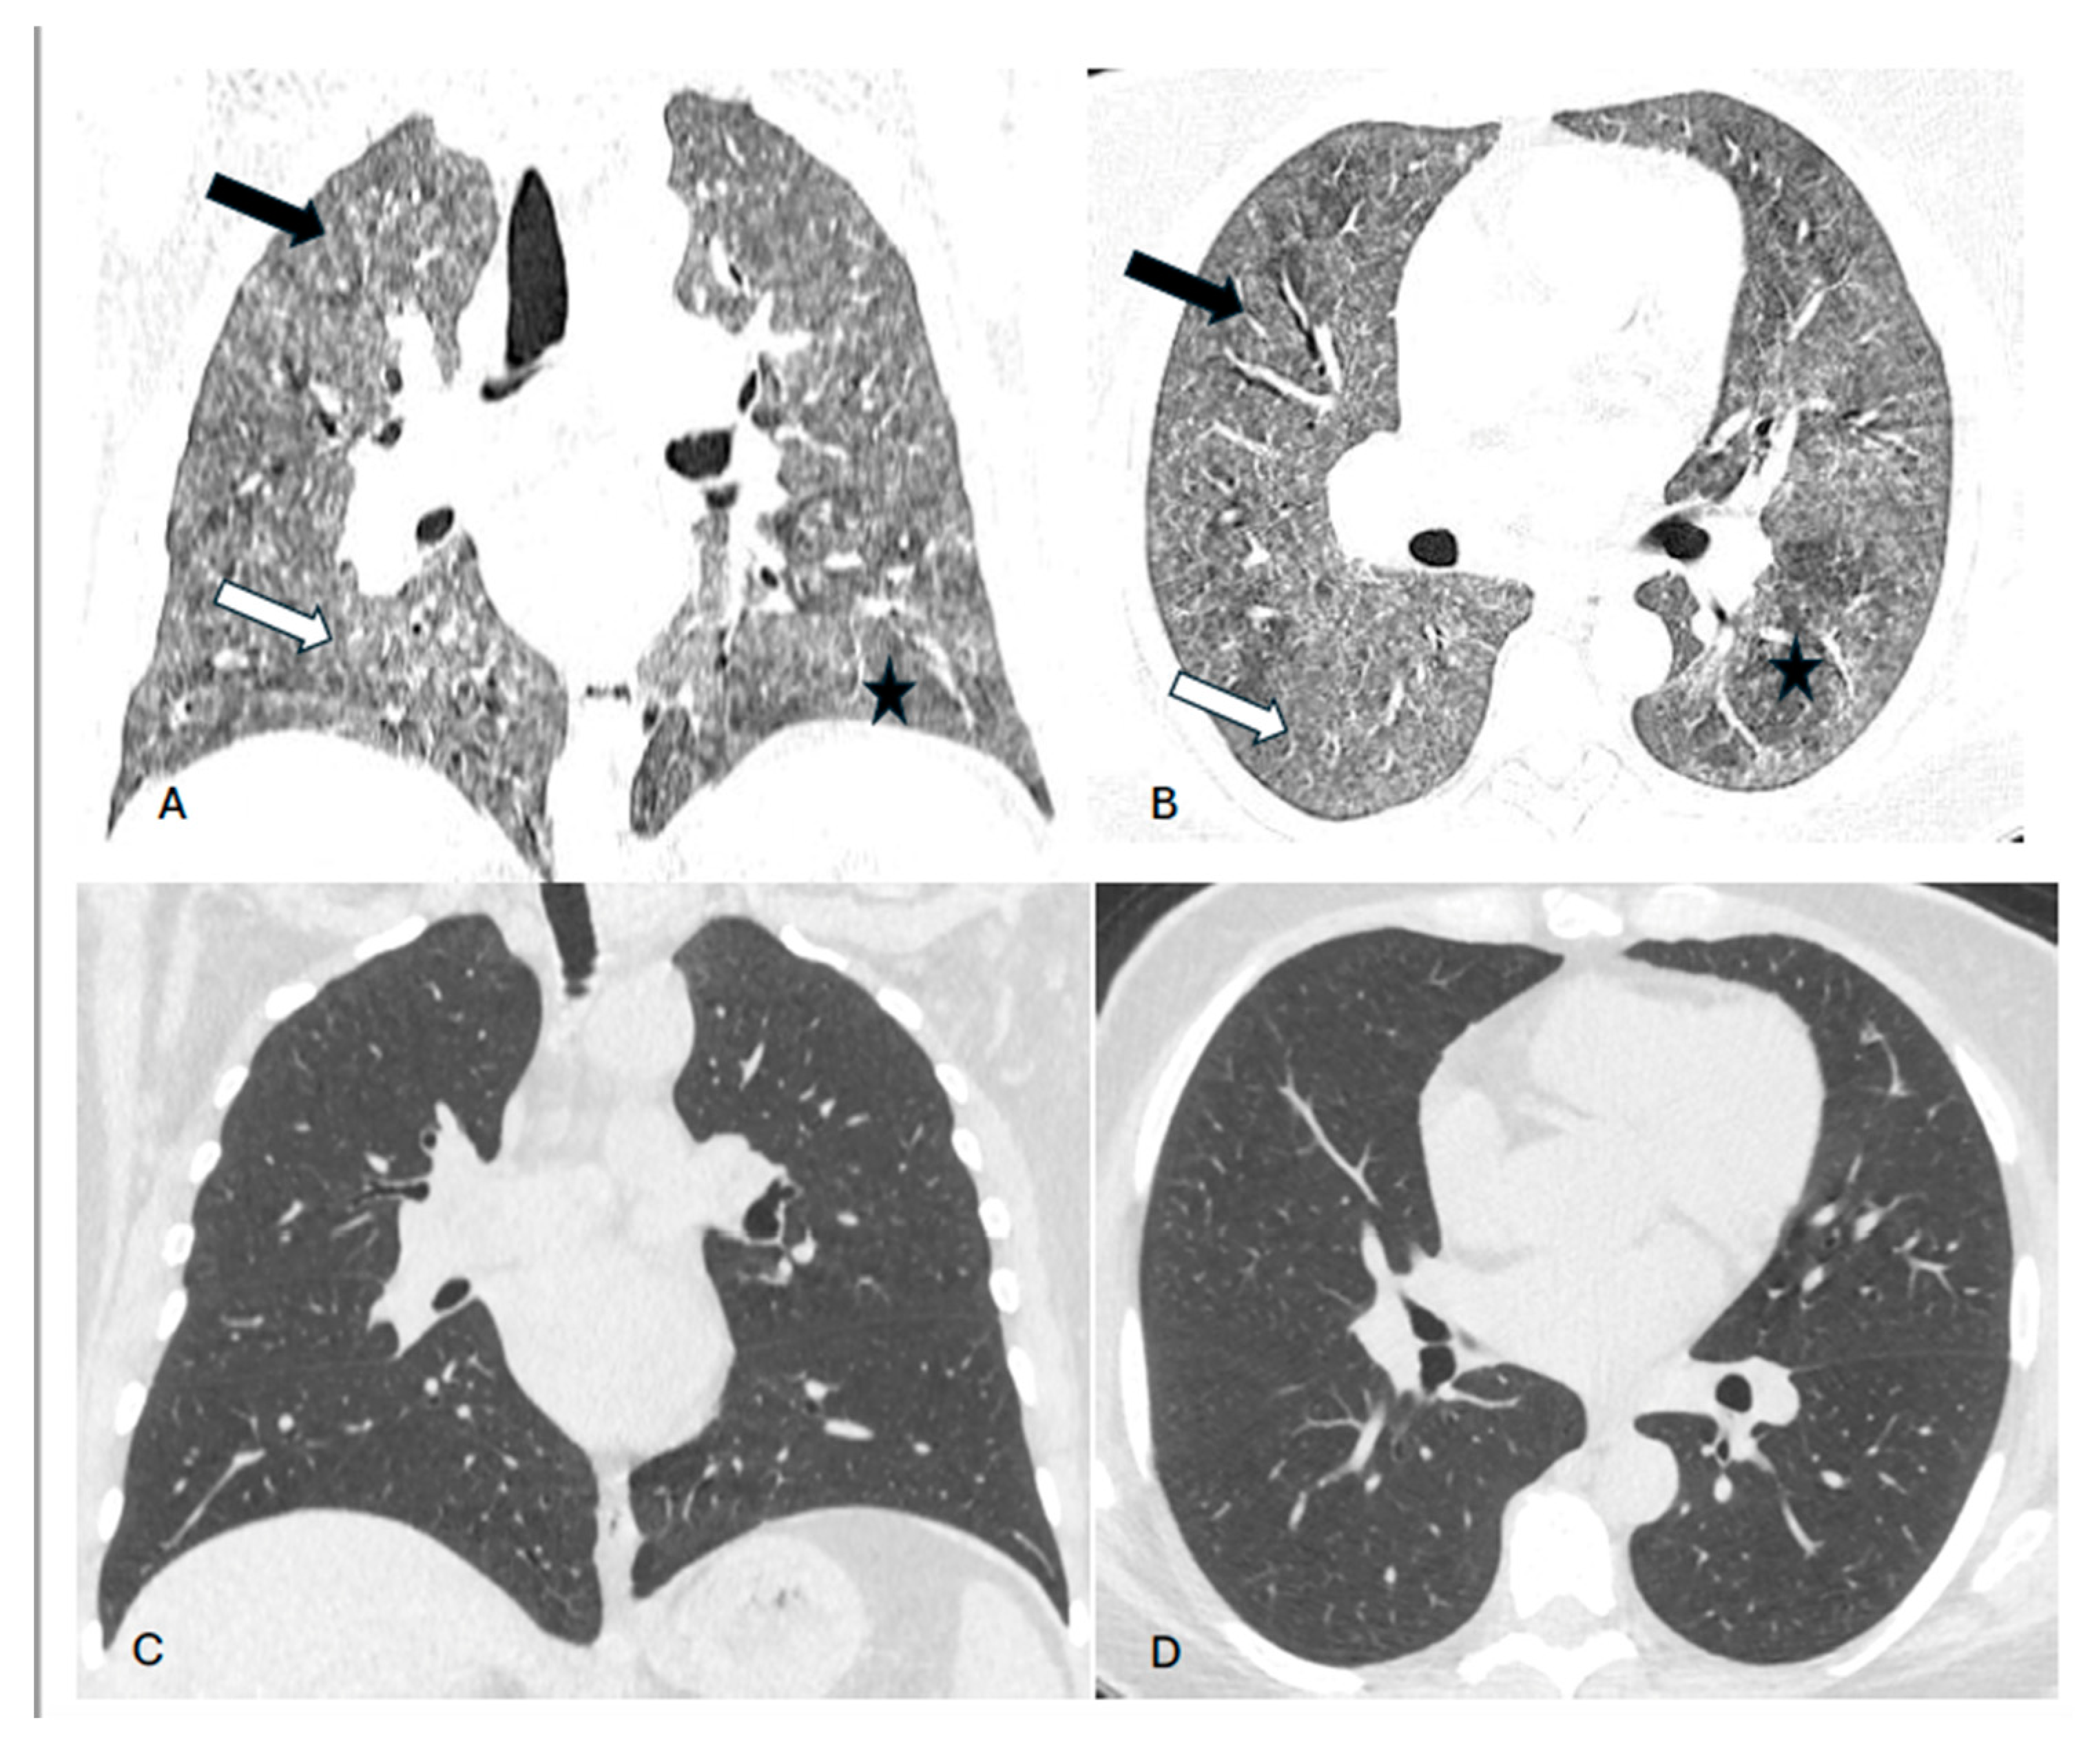

Background. Hypersensitivity pneumonitis (HP) is an increasingly recognized interstitial lung disease, developing as a result of exposition to inhaled, mostly organic, antigens. Two types of the disease are presently distinguished based on HRCT pattern and/or lung biopsy: fibrotic and non-fibrotic (non-fHP). Complete antigen avoidance is the principle of non-fHP treatment. The indications for steroids use in non-fHP depend on the clinical course of the disease. Case presentations. We present three patients in whom acute respiratory failure was diagnosed as the first sign of non-fHP. Intravenous prednisolone, followed by oral therapy with prednisone in diminishing doses, resulted in marked clinical improvement. Respiratory failure subsided within a few days, but regression of lung opacities lasted from 3 to 7 months. In one patient, the discrete reticular opacities, suggestive of the early phase of lung fibrosis, were present on HRCT, but complete regression of lung disease was achieved in the course of treatment. The patients were instructed to avoid antigens exposure; nevertheless, in one of them, a relapse of the disease, requiring a temporal increase of prednisone dose, was observed. Conclusions. Non-fHP may present as sudden-onset hypoxemic respiratory failure. In such patients, the diagnosis is based on medical history concerning the exposition to inciting antigens and characteristic HRCT pattern. Intravenous therapy with prednisolone results in quick resolution of respiratory failure, and BAL performed with a few days of delay may still be of diagnostic value. Ground glass opacities and air trapping may persist for months from exposure.